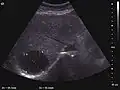

The ultrasound appearance is a well defined lesion, with very thin, almost unapparent walls, without circulatory signal at Doppler or CEUS investigation. The content is transonic suggesting fluid composition. The presence of membranes, abundant sediment or cysts inside is suggestive for parasitic, hydatid nature. Posterior from the lesion the acoustic enhancement phenomenon is seen, which strengthens the suspicion of fluid mass. They typically displace normal liver vessels but no vascular or biliary invasion occurs.

Liver cyst -